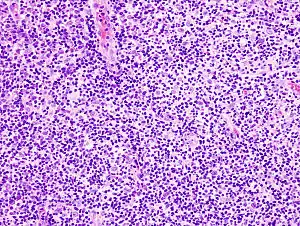

Transtornos linfoproliferativos ou Síndrome linfoproliferativa referem-se a várias condições em que os linfócitos se proliferam em quantidades excessivas. Essas células invadem a pele e um dos primeiros sintomas pode ser pele seca, escamosa com erupções e coceira. Os gânglios linfáticos e o baço podem inflamar e ser palpáveis. Podem causar anemia, hemorragias por falta de plaquetas (plaquetopenia) e imunodeficiência.